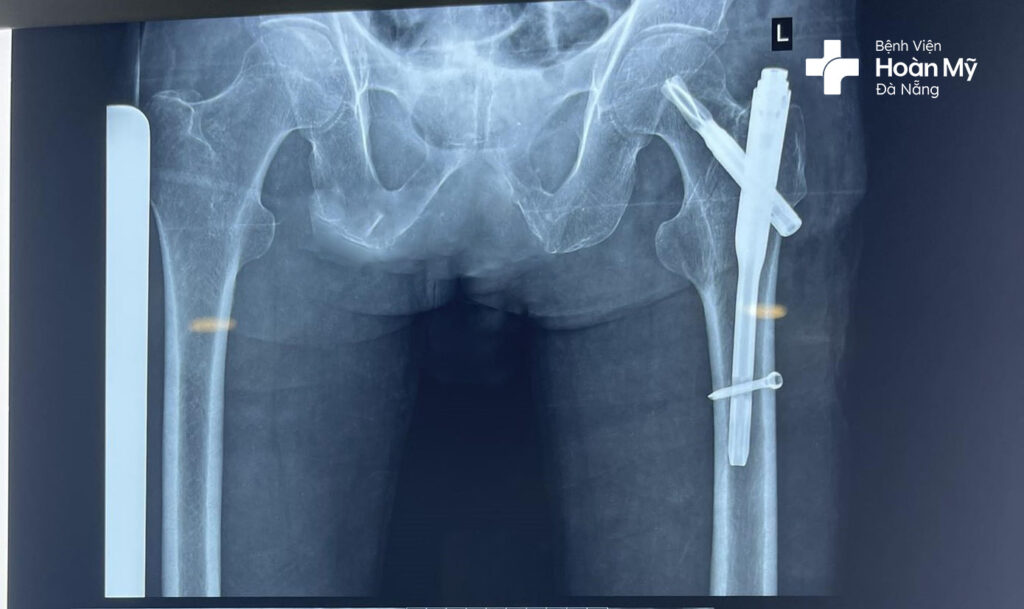

Hình ảnh kết hợp xương bằng đóng đinh nội tủy sau phẫu thuật cho người bệnh

Ca phẫu thuật được thực hiện thành công sau 40 phút tiến hành với vết mổ nhỏ 2-3 cm, người bệnh ít mất máu.

Ở ngày thứ 1 sau phẫu thuật, người bệnh đã bắt đầu với các bài tập phục hồi chức năng, tập đi lại. Đến ngày thứ 3, người bệnh đã có thể tự đi lại với khung tập đi, không cần người hỗ trợ. Ngày thứ 5, người bệnh được cho xuất viện.